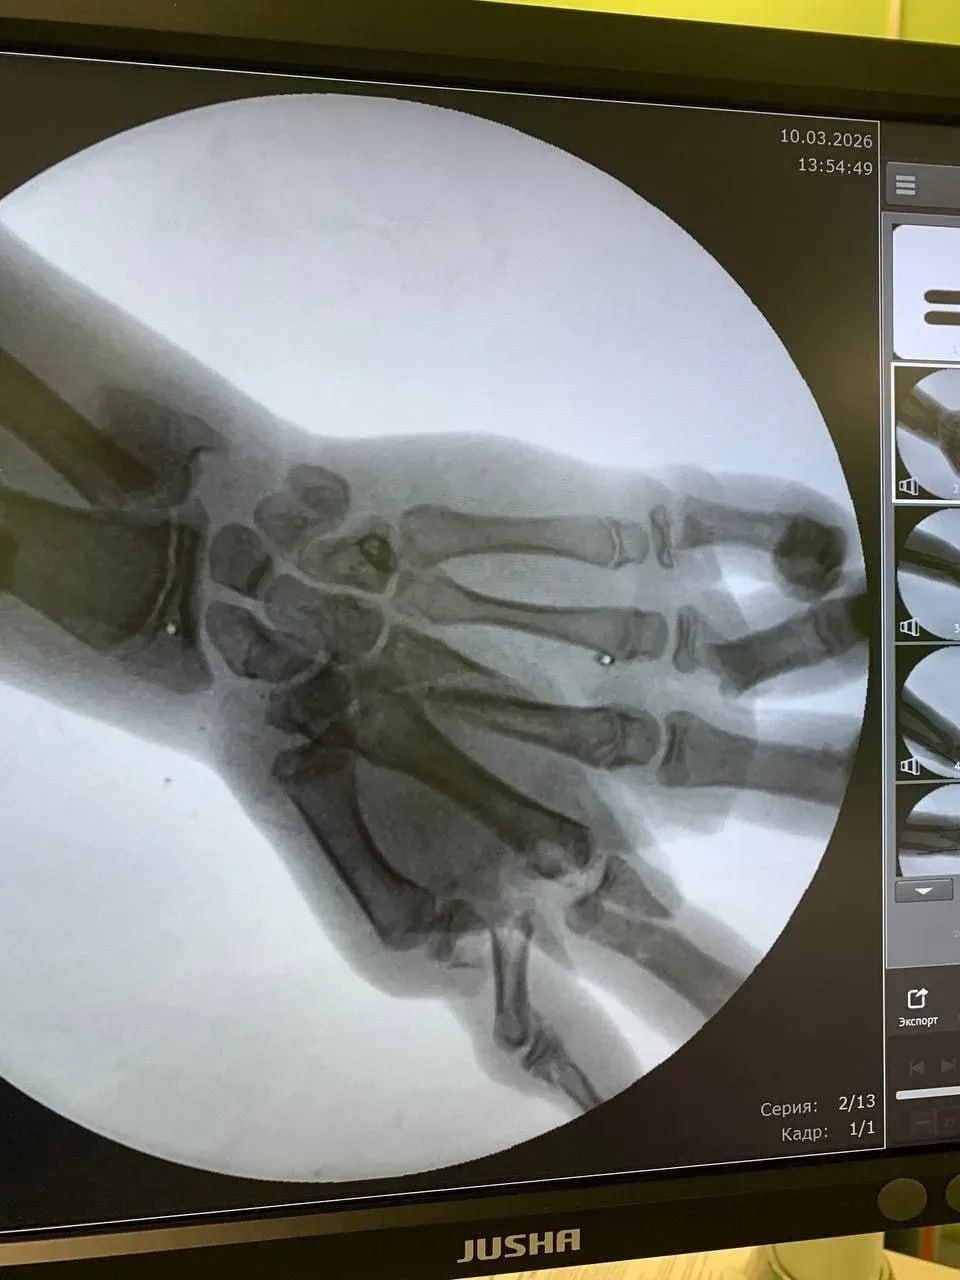

Врачи в Калининграде по частям собрали кисть ребенка, в руках которого взорвался снаряд.

Подросток, не понимая, что это снаряд, пытался распилить его болгаркой. Взрыв спровоцировал в кисти множественные переломы костей и сильнейшее кровотечение.

"В итоге благодаря профессионализму и слаженным действиям медиков кисть, которую без преувеличения им пришлось собирать буквально по частям, удалось сохранить", - рассказали в областном минздраве.